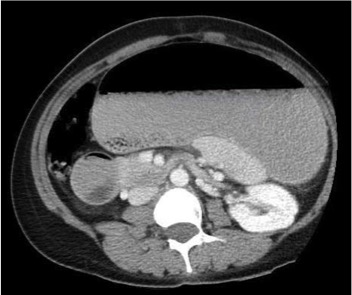

After initial resuscitation with an intravenous (IV) bolus of normal saline, the patient was kept nil orally with maintenance IV fluids (0.45% sodium chloride with 5% dextrose). Abdominal radiographs revealed marked gastric distension with small bowel ileus, indicating possible gastric outlet obstruction or gastric volvulus (Figures 2 and 3). Contrast-enhanced computed tomography (CT) scans of her abdomen and pelvis showed severe dilatation of the stomach and the first and second parts of the duodenum and a collapsed distal small bowel (Figures 4 and 5). These findings were consistent with small bowel obstruction at the level of the mid or distal duodenum, possibly due to volvulus or superior mesenteric artery syndrome (SMAS). The radiographs also confirmed lumbar dextroscoliosis and severe pectus excavatum. The decision was made to perform an urgent laparotomy to relieve her intestinal obstruction.

Figure 5. CT of the abdomen and pelvis, transverse view, showing severe dilatation of the stomach and the first and second parts of the duodenum, along with a collapsed distal small bowel.